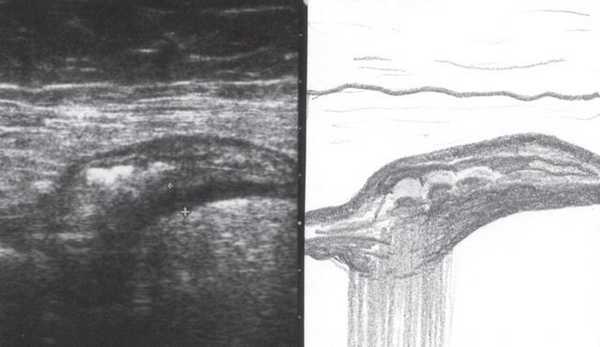

Во время контрольного УЗИ через 6 мес при осмотре левой подвздошной области толщина стенок нисходящего отдела толстой и сигмовидной кишки не превышала 3-5 мм (рис. 6, а, б), при наблюдении в течение 1 года признаков рецидива не отмечено.

Рис. 6. Эхографическая картина толстой кишки. Контрольное трансабдоминальное исследование конвексным датчиком 3,5 МГц через 6 мес.